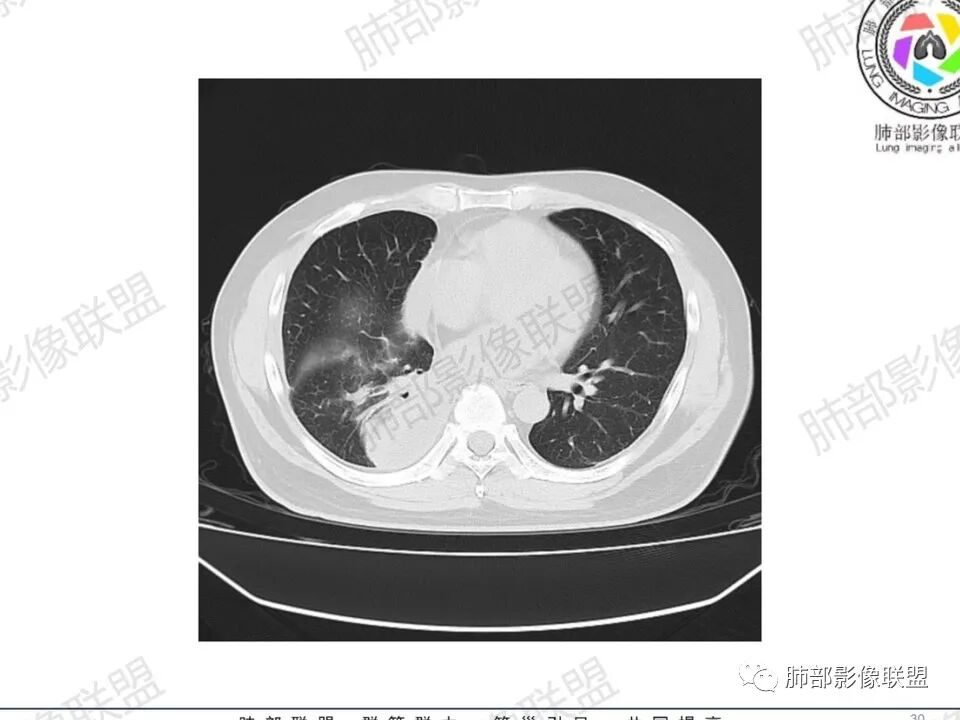

双肺多发结节,胸膜下为主,部分可见空洞。左肺上叶尖后段结节较大,分叶毛刺,周围可见长条索及小斑片影,内空洞比较光滑,内侧壁可见支气管通过。右肺下叶后基底段不张实变,后侧积液,右侧水平裂积液,右侧膈胸膜纵膈胸膜增厚积液,右侧侧胸膜肥厚,考虑1:一元金葡。2二元:金葡,左肺上叶结核。

男,45岁,左手指红肿疼痛两天,右侧胸壁疼痛伴发热12小时入院。患者急性起病,胸部CT示双肺多发结节,部分伴空洞,空洞壁较光滑,右侧胸腔积液,考虑感染性病变,金葡菌加SPE可能

感觉还是金葡入血形成SPE可能性较大,胸水+楔形影+胸膜结节

中年男性,左手中指及胸壁疼痛伴发热来诊,影像见双肺多发结节,胸膜下分布为主,部分结节可见空洞,边缘模糊。左肺上叶尖后段结节较大。右肺下叶后基底段不张实变,右侧叶间裂及右侧胸腔积液,右侧侧胸膜肥厚。考虑金葡菌感染,血播SPE。

两肺多发结节空洞,随机分布,右肺下叶部分病灶实变并胸膜腔少量积液,有皮肤破溃,手指疼痛,发热,考虑感染性变,金葡可能性大。

空洞内壁光滑,偏心厚壁空洞,张力高

胸水,部分包裹